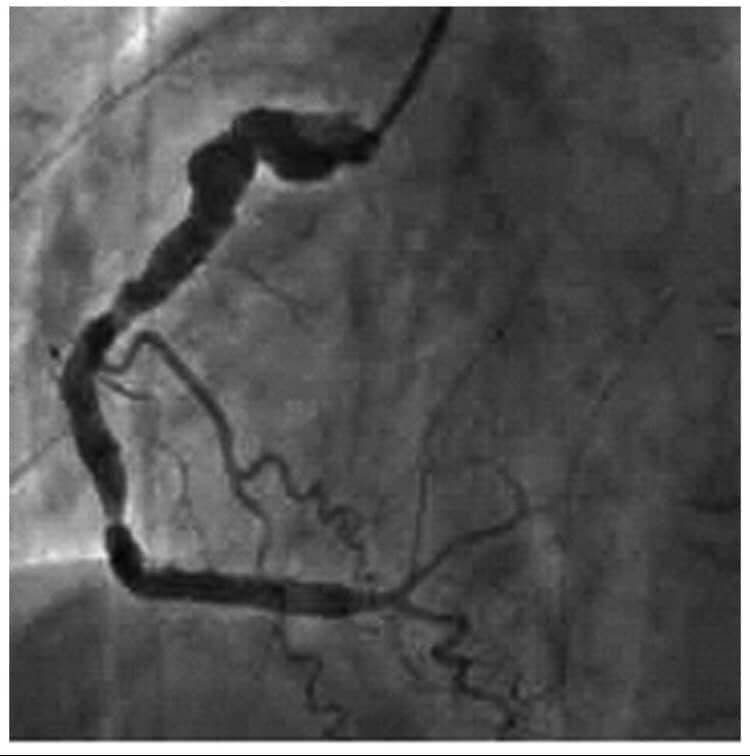

١- الألم الصدري عند الجهد او ما يعرف بالخناق الصدري المستقر على الإجهاد وهو الم يصيب المريض عند القيام بمجهود جسدي معين كمشي حوالي مئتي متر مثلا او صعود ثلاث طوابق او حمل ثقل معين. ويكون هذا الألم بشكل الم في اعلى الصدر والعنق والفك واحيانا في البلعوم والرقبة والكتف الأيسر ويمتد احيانا حتى الذراع الأيسر . وستمر هذا الالم لمدة ٣ او ٤ دقائق على ان يزول نهائيا بعد ذلك . ويحصل كل مرة على ذات مستوى الإجهاد ويتنهي مع توقف الإجهاد ليعود ويظهر مع مع معاودة الجهد ولذات المسافة او الجهد الذي قام به المريض ولذلك نقول عنه انه مستقر لأنه يظهر عند القيام ب ذات الجهد . وهو غالبا ما يكون ناتج عن إنسداد شريان واحد من الشرايين التاجية للقلب ونشخصه بسهولة عبر الوصف والفحص السريري وتخطيط القلب العادي EKG الذي قد يظهر بعض العلامات او عن طريق إجراء فحص الإجهاد: Stress test حيث تظهر ذات علامات الألم مع الركض السريع على سجادة فحص الجهد او على الدراجة الهوائية التي نستعملها من اجل ذلك. وعند إجراء التمييل او القسطرة Coronarograpgy يظهر ان هناك إنسداد واحد او إصابات على شريان واحد من الشرايين التاجية للقلب وعادة ما تكون هذه الإنسدات مهمة وتتراوح بين ٧٠ و ٩٠ او ٩٥ بالمئة ولكنها قطعا لا تكون إنسدادات كاملة اي مئة بالمئة . ومن الممكن في معظم الاحول علاجه بواسطة عملية التوسيع بالبالون والروسور وبعد ذلك تزول كل هذه العلامات او الأعراض ولكن المريض يجب ان يتناول بعدها بعض الادوية التي سنذكرها لاحقا. وطبعا عليه ايضا مراقبة عوامل الخطورة مثل إيقاف التدخين ومراقبة الدهنيات في الدم ومرض السكري وارتفاع الضغط وعلاج كل هذه الامراض بأدويتها المناسبة والقيام بتمارين رياضية شبه يومية او لثلاث مرات في الاسبوع.